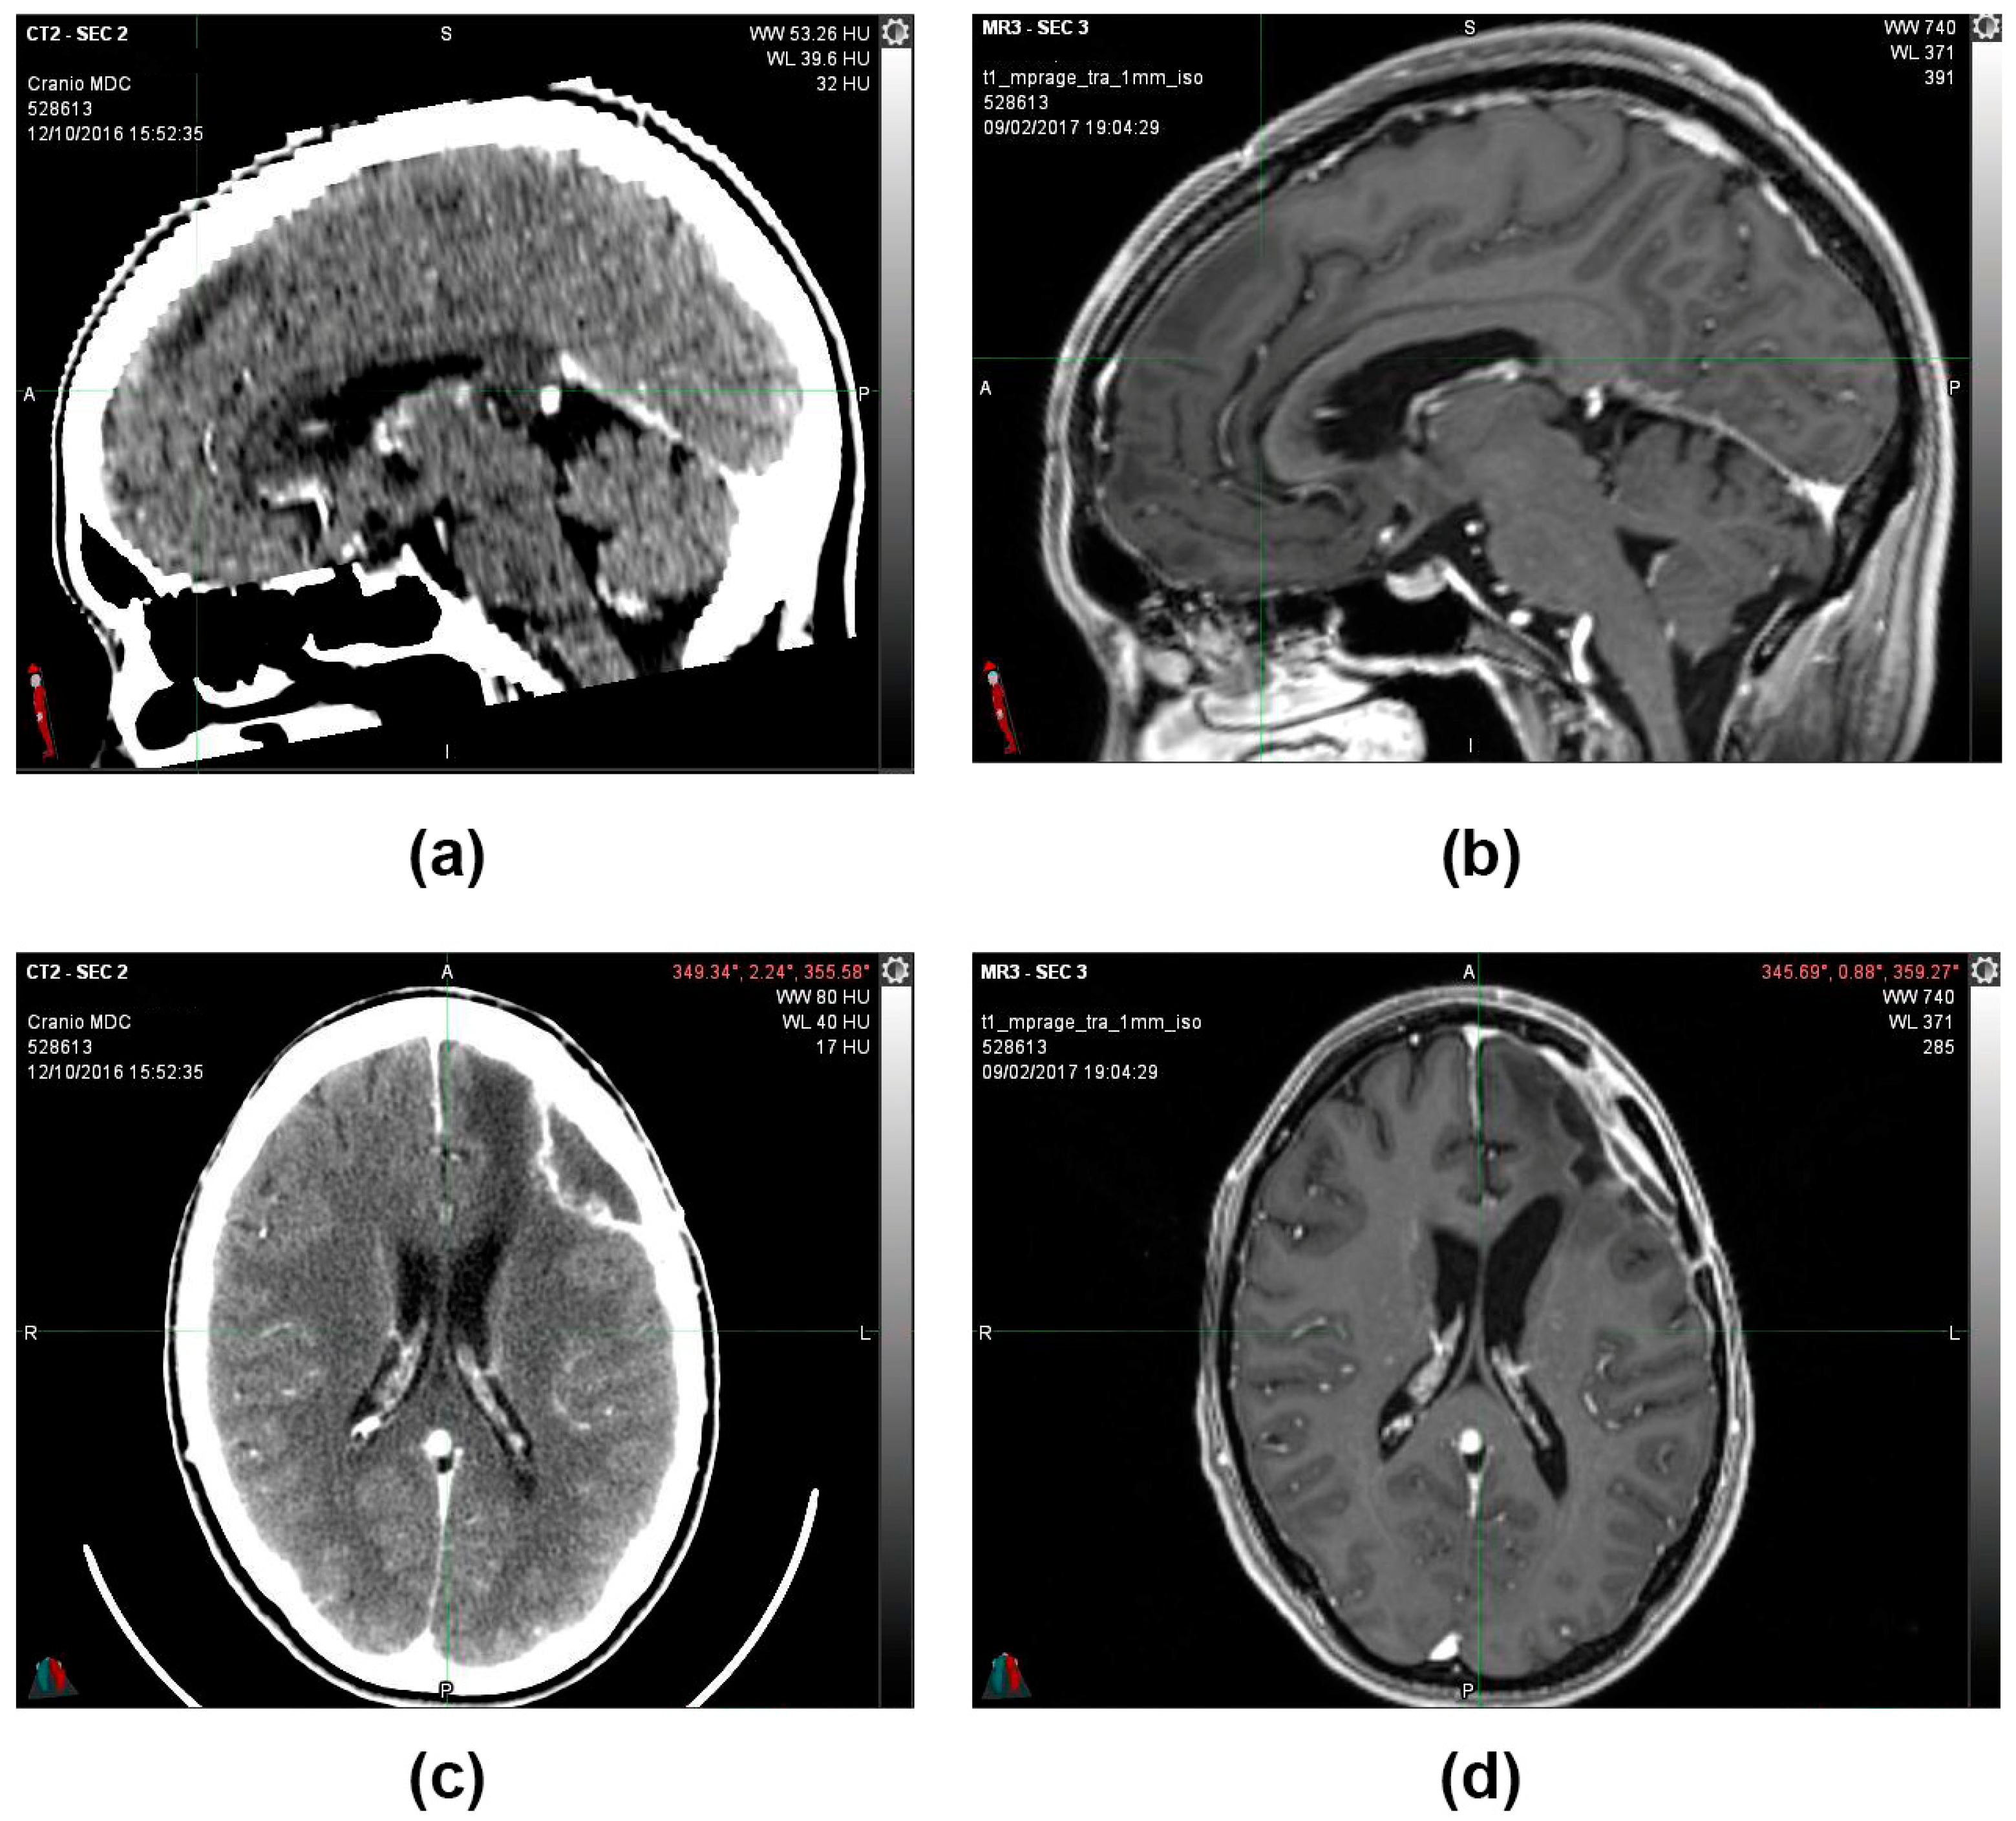

During the follow-up, quarterly visits, clinical-instrumental checks, and monthly blood and biochemistry tests were carried out. At the end of the first cycle of O2O3 therapy (9 February 2017), the 2 cm residual tumor mass that was present 3 months before was no longer visible on the brain magnetic resonance imaging (MRI) (Figure 3), and the stable-negative tumor mass was confirmed with the MRI on 11 October 2022 (Figure 4).

Figure 3.

(a,c) 12 October 2016, CT scan image with contrast medium. Posterior to the surgical cavity, an approximately 2 cm hyperdense solid nodule is present (b) 9 February 2017, MRI T1 sequence with contrast medium. After the first cycle of O2O3 therapy, the 2 cm residual tumor mass that was present 3 months before was no longer visible (d) 9 February 2017, MRI image sequence in Fluid-attenuated inversion recovery (FLAIR).